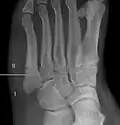

For several reasons, a Jones fracture may not unite. The diaphyseal bone (zone II), where the fracture occurs, is an area of potentially poor blood supply, existing in a watershed area between two blood supplies. This may compromise healing. In addition, there are various tendons, including the fibularis brevis and fibularis tertius, and two small muscles attached to the bone. These may pull the fracture apart and prevent healing.

Zones I and III have been associated with relatively guaranteed union and this union has taken place with only limited restriction of activity combined with early immobilization. On the other hand, zone II has been associated with either delayed or non-union and, consequently, it has been generally agreed that fractures in this area should be considered for some form of internal immobilization, such as internal screw fixation.

These zones can be identified anatomically and on x-ray adding to the clinical usefulness of this classification.[21] Surgical intervention is not, by itself, a guarantee of cure and has its own complication rate. Other reviews of the literature have concluded that conservative, non-operative, treatment is an acceptable option for the non-athlete.[22]

-

Anatomy of the fifth metatarsal. -

3 zone description -

2 zone description